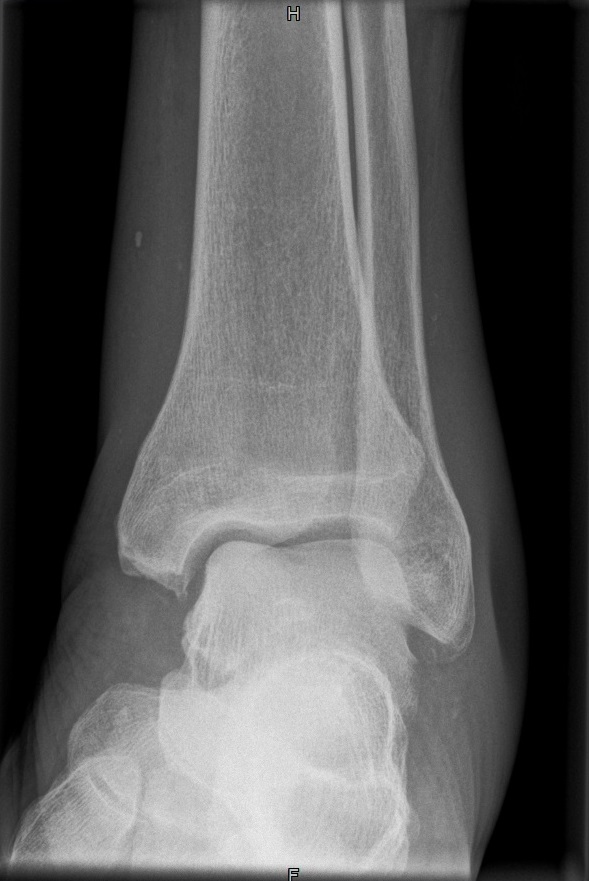

OSG a.p.

129_5.jpg

Fehler

Außenrotation bzw ungenügende Rotation des Fußes nach innen. Der mediale Gelenkspalt projiziert sich besonders schön frei, hingegegen ist der laterale Spalt verschattet.

Abhilfe

Fuß weiter nach innen drehen lassen, bis beide Malleolen auf einer Höhe parallel zum Film stehen.